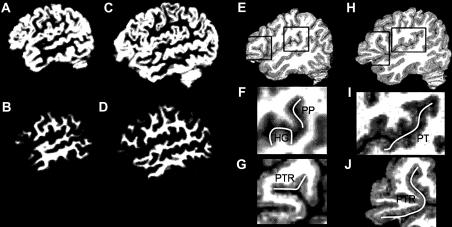

Biological and behavioral differences between the sexes range from obvious to subtle or nonexistent. Neuroanatomical differences are particularly controversial, perhaps due to the implication that they might account for behavioral differences. In this sample of 200 men and women, large effect sizes (Cohen's d > 0.8) were found for sex differences in total cerebral gray and white matter, cerebellum, and gray matter proportion (women had a higher proportion of gray matter). The only one of these sex differences that survived adjustment for the effect of cerebral volume was gray matter proportion. Individual differences in cerebral volume accounted for 21% of the difference in gray matter proportion, while sex accounted for an additional 4%. The relative size of the corpus callosum was 5% larger in women, but this difference was completely explained by a negative relationship between relative callosal size and cerebral volume. In agreement with Jancke et al., individuals with higher cerebral volume tended to have smaller corpora callosa. There were few sex differences in the size of structures in Broca's and Wernicke's area. We conclude that individual differences in brain volume, in both men and women, account for apparent sex differences in relative size.

两性之间的生物学和行为差异范围从明显到微妙或不存在。神经解剖学差异尤其具有争议性,这可能是因为它们可能被认为是行为差异的原因。在这个由200名男性和女性组成的样本中,发现大脑总体灰质和白质、小脑以及灰质比例的性别差异具有较大效应量(科恩d值>0.8)(女性的灰质比例更高)。在对脑容量的影响进行调整后,这些性别差异中唯一仍然显著的是灰质比例。脑容量的个体差异占灰质比例差异的21%,而性别差异又额外占4%。女性胼胝体的相对大小比男性大5%,但这种差异完全可以由胼胝体相对大小与脑容量之间的负相关关系来解释。与扬克等人的研究一致,脑容量较大的个体往往胼胝体较小。布洛卡区和韦尼克区结构的大小几乎没有性别差异。我们得出结论,男性和女性的脑容量个体差异导致了相对大小上明显的性别差异。